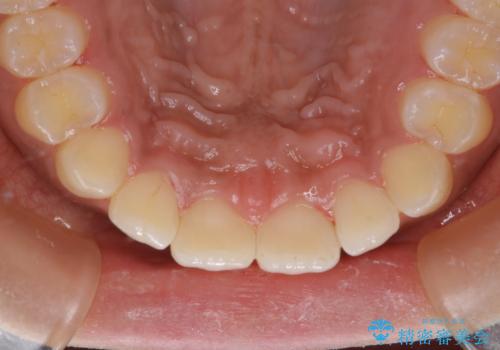

タバコのステインを徹底的に除去

PMTC60分コースを行いました。

PMTCでは、歯の表面の凸凹にミネラルを補給して、ツルツルの表面に仕上げます。定期的にPMTCを行うことにより、歯質の強化になり着色がつきにくい状態になります。

普段の飲食物・歯磨き・生活習慣・喫煙の有無などにより着色の付き具合には個人差があります。どれくらいの頻度で行うことがベストかは、その都度担当の歯科衛生士とご相談します。